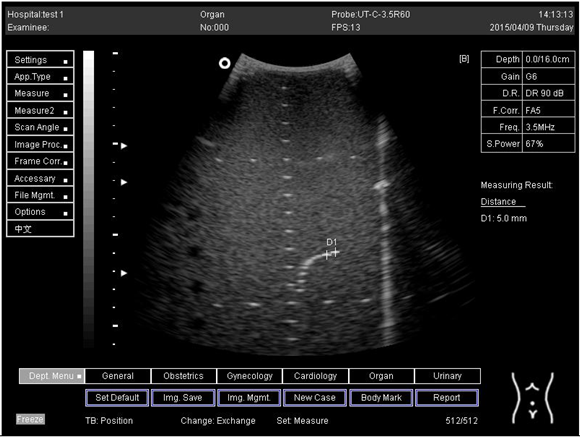

16.0Axial resolution

Biomimetics 07 00130 i025

D1 = 5.6

D2 = 4.1

D3 = 3.0

Lateral resolution

Biomimetics 07 00130 i026

D1 = 5.0